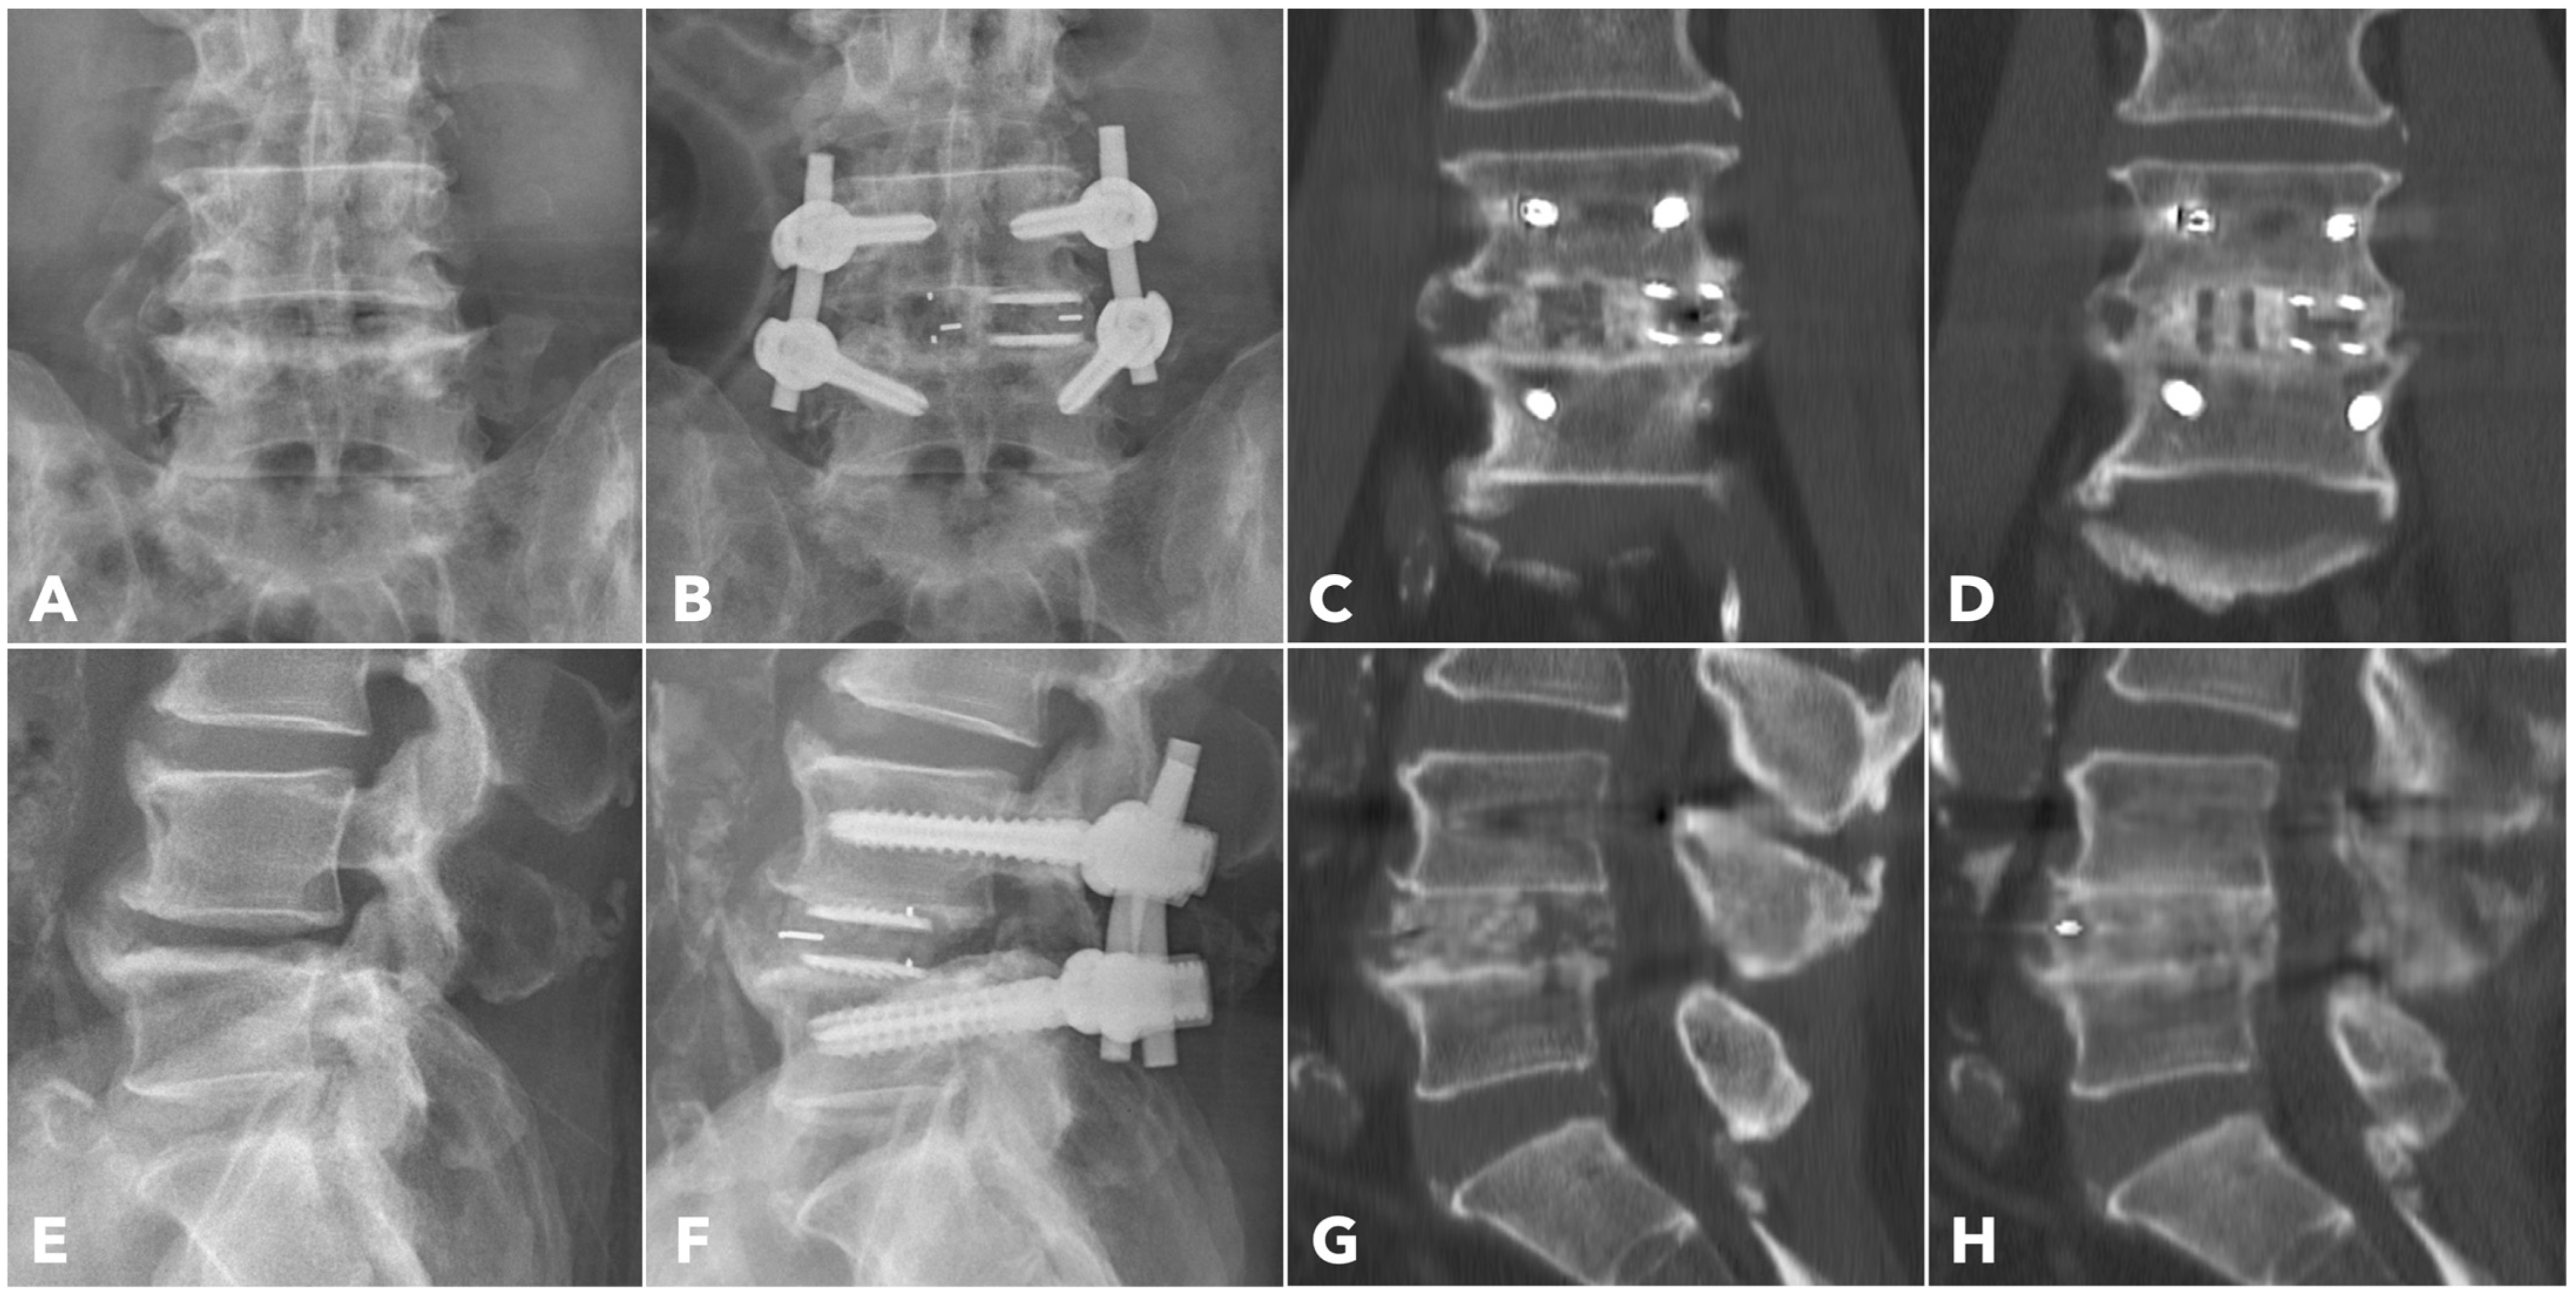

Among the segments evaluated by CT at one year (56.7% in MISTLIF vs. 67.4% in BETLIF, q = 0.216), the BETLIF group showed significantly higher rates of bridging bone in the sagittal (96.6% vs. 88.2%, p = 0.027) and coronal planes (93.3% vs. 82.4%, p = 0.025). The overall fusion success rate (Bridwell Grade I or II) was significantly higher in the BETLIF group (93.3% vs. 82.4%, p = 0.025). However, these statistical significances were eliminated after applying the Benjamini–Hochberg correction to control the FDR. Furthermore, a substantially higher proportion of BETLIF cases were classified as Bridwell Grade I (73.3% vs. 19.6%, q < 0.001), indicating superior fusion quality (Figure 6 and Figure 7).

Figure 6. A 67-year-old male patient underwent BETLIF at L4-5 due to recurrent lumbar disc herniation and painful disc degeneration (A,E). The postoperative X-rays showed restoration of the disc height with double cages in the disc space (B,F). The immediate postoperative CT scan demonstrated the cage positions and no violation of the bony endplates (C,G). The 1-year CT scan revealed Bridwell grade I solid fusion with remodeling of the bone graft (D,H).

Figure 7. A 62-year-old male patient underwent BETLIF at L4-5 due to painful disc degeneration with restoration of the disc height after the surgery (A,B). The postoperative 6-month X-ray showed consolidation of the bone graft (C). The 1-year CT scan revealed Bridwell grade I solid fusion with remodeling of the bone graft at both coronal plane (D) and sagittal plane (F,G) reconstructions. The axial plane reconstruction (E) demonstrated the cage footprint and the fusion bed. The white dashed line indicates the margin of the vertebral body.